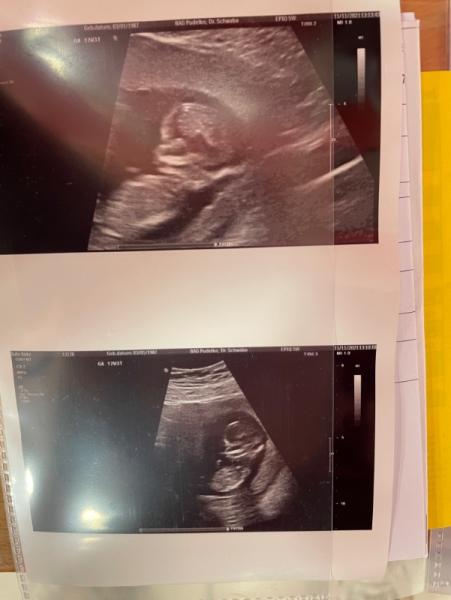

Update zu dem Post :) alles unauffällig Baby gesund und wächst und gedeiht wie es soll

Bild zu